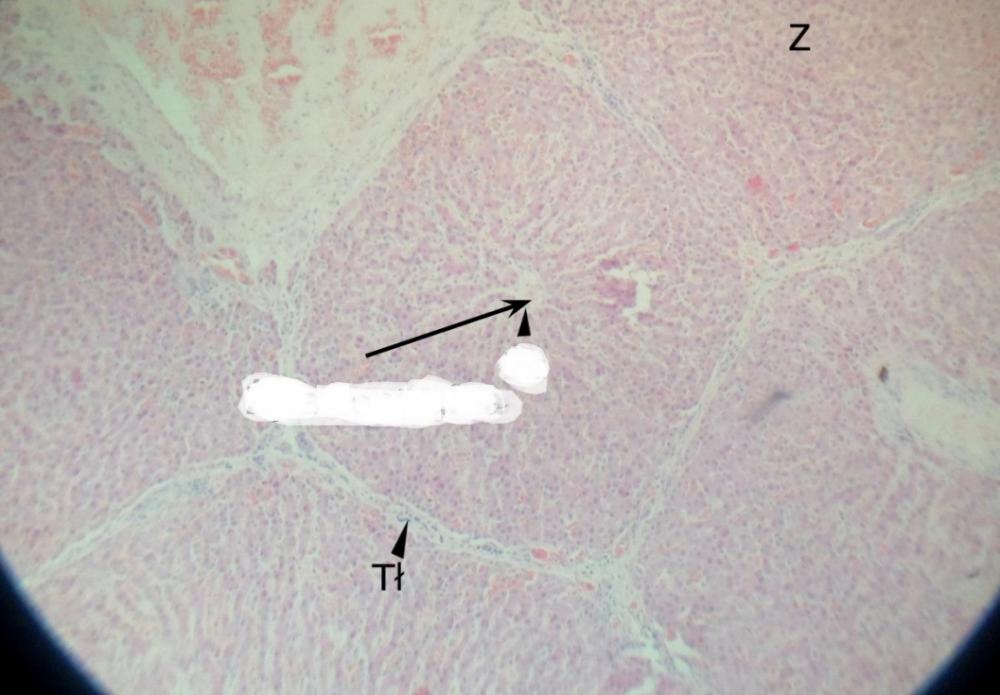

Pytanie 441

żyła centralna (wątroba świni)

Pytanie 442

żyła podzrazikowa (wątroba świni)

Pytanie 443

lokalizacja triad (wątroba świni)